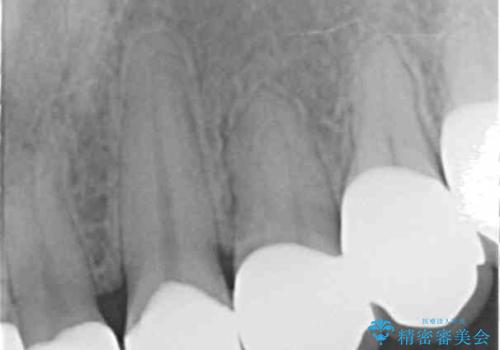

- K-POP(Kポップ)アイドルのような歯にしたいと希望され来院された患者様です。

矯正を途中でやめてしまったとのことで、歯に矯正の接着材が残っており着色も顕著でした。

奥歯の咬合面にはレジンが盛られた状態でした。

見た目と咬み合わせを改善するため、セラミッククラウンによる治療を行いました。